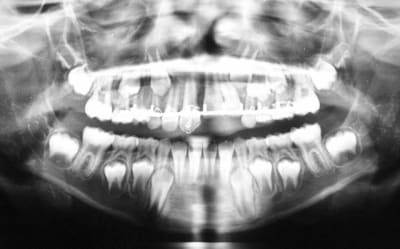

patient 8 ans vu aujourd'hui

chute le 29/08/2006(clermond ferrand)

impaction 21 et 22(21 fracturée au 1/3 coronaire)

luxation totale de 11

réimplantation au bout de 4 h(conservée ds ..rien:compresses sèches mais pas traitée...)

mise en place d'un arc de contention(Duclaux)

contention enlevée il y a 15 jours(dc 4 semaines de contention)

que feriez vous avec 11,sachant qu'il y a ankylose et aucune mobilité mais aussi rhyzalyse importante?

de la 11 obturée aujourd'hui au MTA

compte tenu de la longueur et de la dilacération de la racine ,le but est de reculer l'échéance de la perte de cette dent...,puis ce sera 11 collée sur arc palatin ou bridge collé mais j'aime pas:):),puis implant

21 et 22 sous surveillance